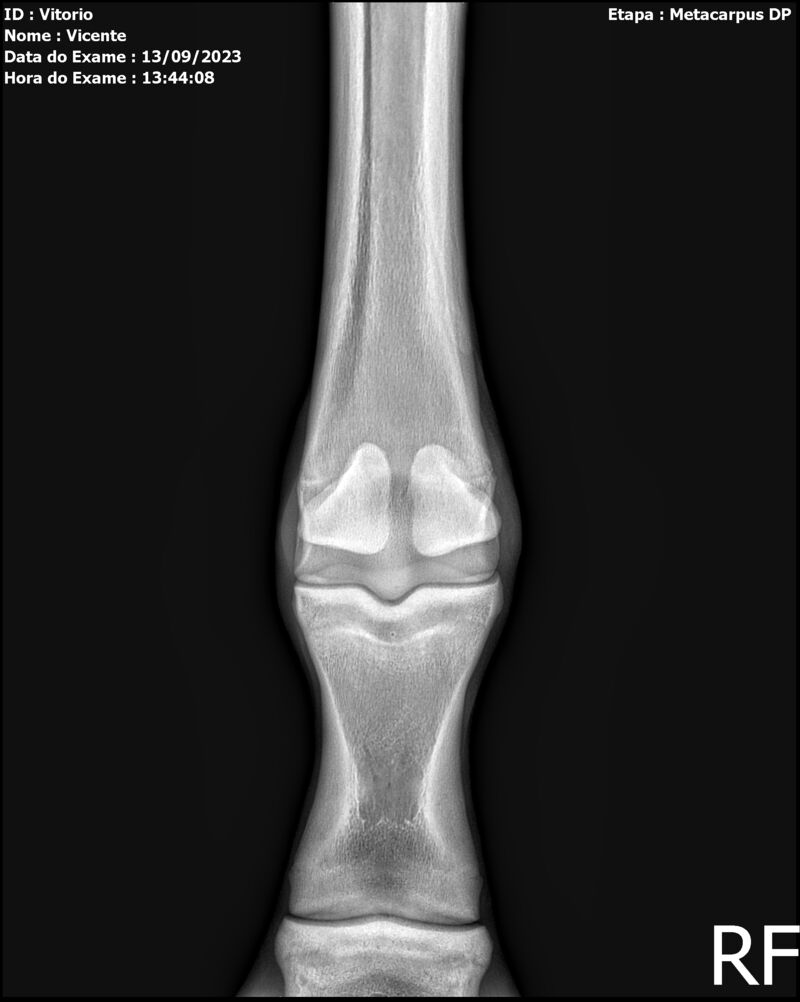

LOTE 13

THUNDER ZC

Raça: BRASILEIRO DE HIPISMO

Sexo: MACHO - POTRO

Nascimento: 17/09/2022

Altura Aproximada: 1,54

Pel.: CASTANHO

Registro: EM AND

Vend.: VICENTE CONTE

Local : PORTO FELIZ/SP